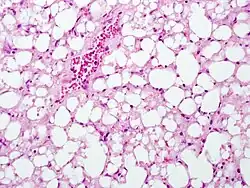

Widespread necrosis in the central venule regions of the liver acinus. Lipid droplets have merged to form lipid lakes.

Mostly viable hepatocytes in the portal area (zone 1) of the liver acinus, with arrows pointing to a necrotic zone on the edge

These H&E pathology slides were taken from an acetaminophen poisoning case involving an adult with a history of alcohol abuse. Case contributed by Dr. Linda Ferrell, UCSF, Department of Pathology.

The second phase occurs between 24 hours and 72 hours following overdose and consists of signs of increasing liver damage. In general, damage occurs in liver cells as they metabolize the paracetamol. Hallmark pathology on liver biopsy includes regions of coagulative necrosis in zone 3 of the liver acinus, around the central venules, as these hepatocytes have higher concentrations of cytochrome P450 enzymes compared to zone 1 hepatocytes surrounding the portal venule of the acinus. Remaining viable hepatocytes frequently show ballooning injury and steatosis.[13] The individual may experience right upper quadrant abdominal pain. The increasing liver damage also changes biochemical markers of liver function; International normalized ratio (INR) and the liver transaminases ALT and AST rise to abnormal levels.[14] Acute kidney failure may also occur during this phase, typically caused by either hepatorenal syndrome or multiple organ dysfunction syndrome. In some cases, acute kidney failure may be the primary clinical manifestation of toxicity. In these cases, it has been suggested that the toxic metabolite is produced more in the kidneys than in the liver.[15]